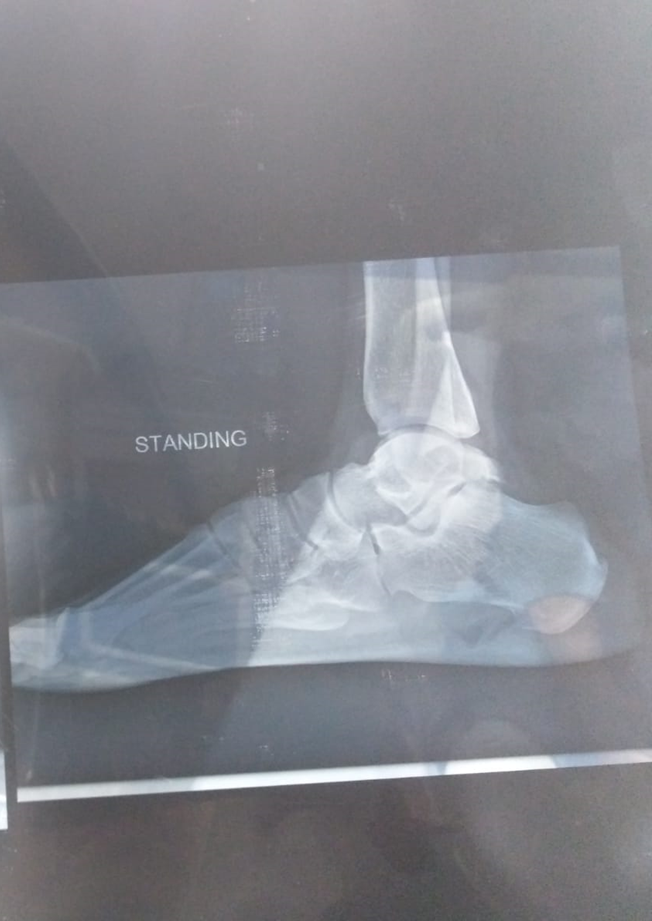

On his first post-op day, a 26-year-old football player presented to the IPD. The patient had a complete, close fracture of the talus bone, which was surgically repaired by the procedure of subtalar joint fusion. There were no pre-op or post-op complications. Patient had a history of foot injury in 2019, which was conservatively managed, but this did not heal his fracture, and he re-injured his foot by that time. Despite the fact that the patient was young and a non-smoker, the only reason for the non-healing of his fracture by conservative means was his early return to sports. The AROM of the associated joints of the lower limb was within functional range prior to surgery, but ankle ROM was limited due to fracture. After the surgery, the AROM of the ankle was not testable due to the cast.